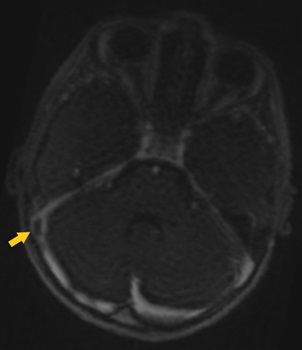

Al ingreso se realizó una RM cerebral con fase venosa, donde se observó una trombosis que afectaba al seno venoso transverso de forma parcial, seno sigmoideo y vena yugular del lado derecho. En la imagen axial TOF 2D (time of flight) (Fig. 1) se observa la presencia de material trombótico en el segmento distal del seno transverso derecho.